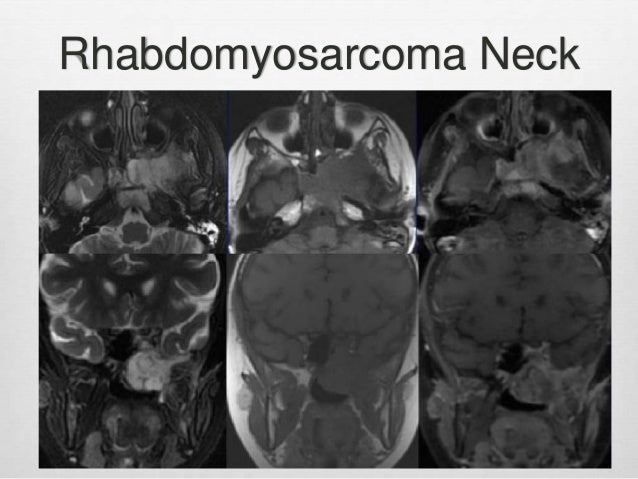

PPT - Pediatric Head And Neck Malignancies PowerPoint Presentation

www.slideserve.com

www.slideserve.com

rhabdomyosarcoma neck presentation pediatric head malignancies ppt powerpoint dna amplification gene cases

rhabdomyosarcoma pancytopenia ppt powerpoint presentation neck